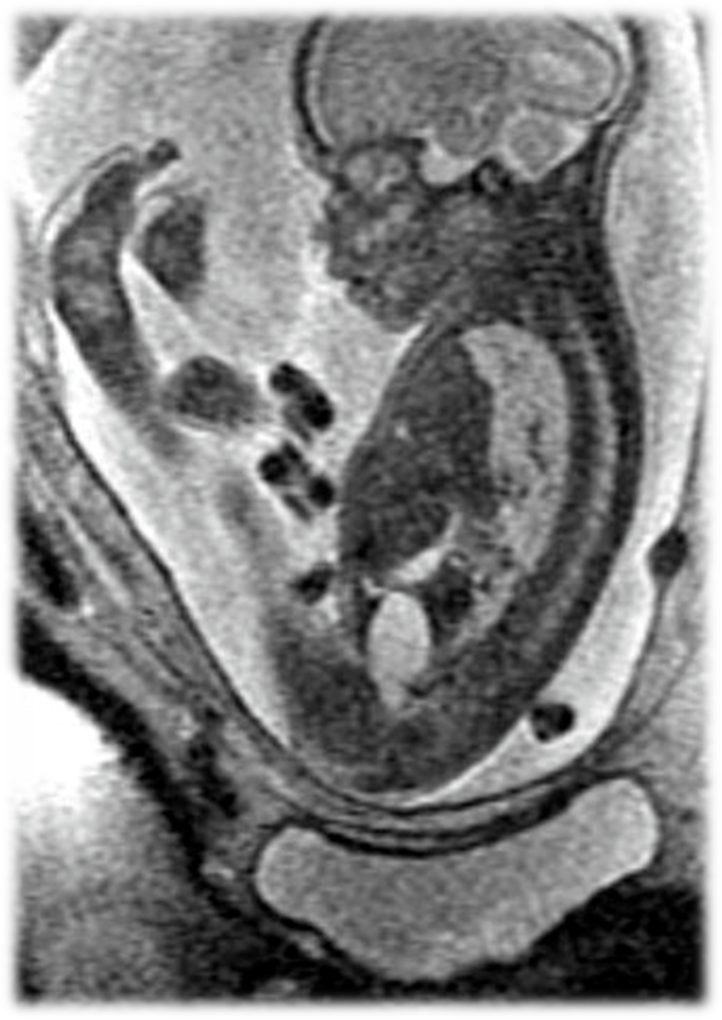

Caudal Regression Syndrome